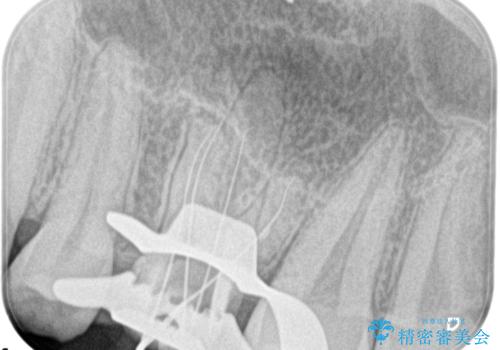

大きい虫歯 根管治療〜オールセラミッククラウン

- 歯が欠けたことを主訴に来院されました。

再根管治療後、歯周外科を行い、オールセラミッククラウンにて修復処置を行っております。

根管治療を行った大臼歯は速やかに被せ物の治療を行うことが必要です。